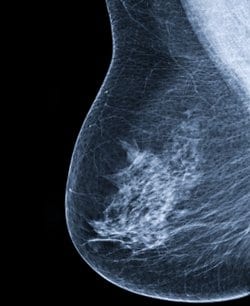

כריתת הגידול משפרת את סיכויי ההישרדות של נשים עם סרטן שד חיובי ל- HER2 המצוי ב- stage 4.

במסגרת המחקר הרטרוספקטיבי נבדקו הרשומות של כ- 3200 נשים עם סרטן שד חיובי ל- HER2 המצוי ב- stage 4. כ- 90% טופלו בכימותרפיה או אימונותרפיה, 38% קיבלו טיפול אנדוקריני, ו- 32% הקרנות. יתר על כן, כשליש עברו כריתה כירורגית של הגידול הראשוני.

לאורך חציון מעקב של 21 חודשים, הטיפול הכימותרפי/אימונותרפי והאנדוקריני הפחיתו באופן מובהק את שיעורי התמותה. יתר על כן, נשים שאף עברו ניתוח הציגו סיכון נמוך ב- 44% לתמותה, בהשוואה לנשים שלא עברו ניתוח.